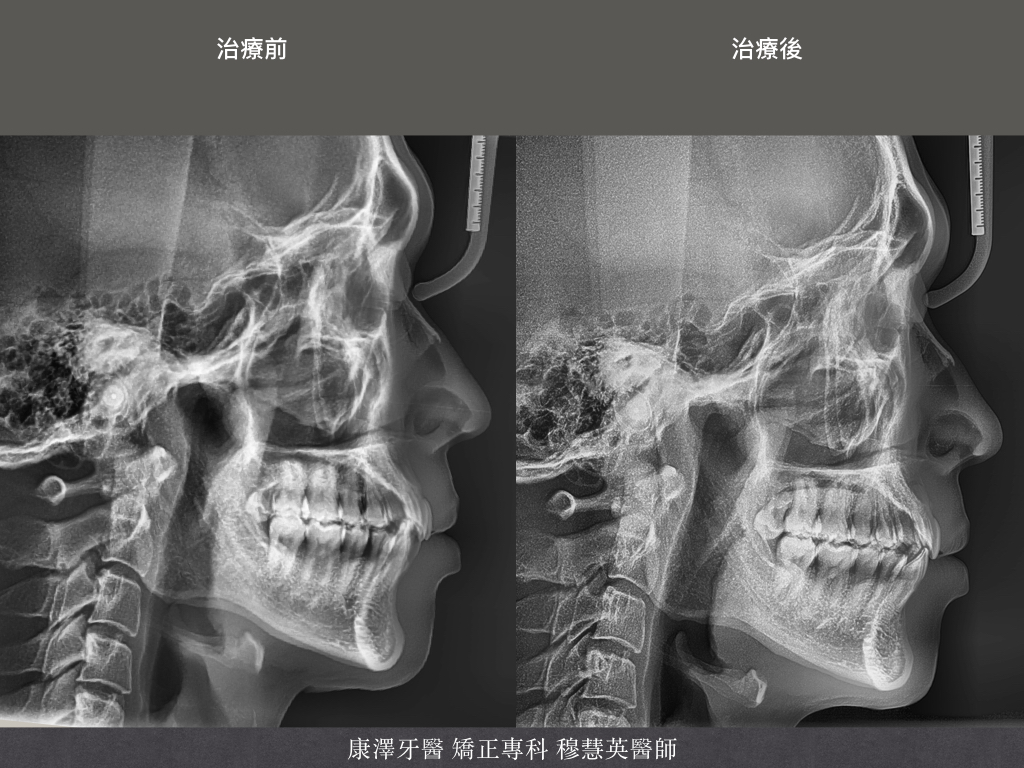

以下展示完成案例